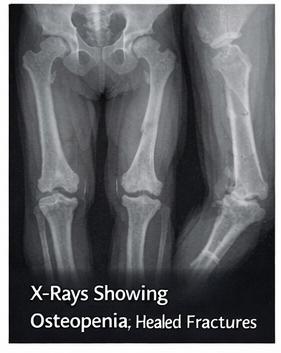

Clinically, OI presents with recurrent fractures following minimal or no trauma, skeletal deformities, growth retardation, and characteristic extraskeletal features such as blue sclerae, dentinogenesis imperfecta, and hearing impairment. The disease is classified into several types based on clinical severity, radiographic findings, and genetic etiology. Despite advances in supportive care and pharmacologic therapy, OI remains a lifelong condition requiring long-term follow-up and multidisciplinary management.

On physical examination, the child had short stature for age and mild bowing of the lower limbs. Blue discoloration of the sclerae was noted bilaterally. Dental examination revealed opalescent teeth suggestive of dentinogenesis imperfecta.

At six-month follow-up, the patient had not sustained any new fractures and demonstrated improved mobility and confidence during physical activity. Repeat radiographs showed improvement in bone mineralization. The child continued to attend regular physiotherapy sessions and remained compliant with treatment.